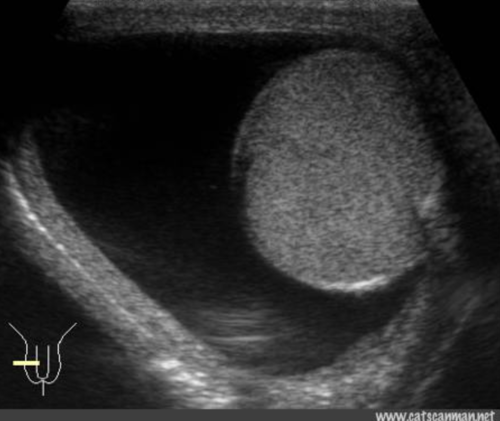

THIS IMAGE REPRESENTS WHICH OF THE FOLLOWING:

testicular trauma

free fluid in the testicle

hydrocele

normal scrotum